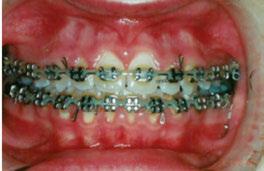

Figures 1A and 1B: Adolescent with anterior open bite: Orthognathic surgery unnecessary post-myofunctional therapy. 1A. Pre-myofunctional therapy: The bite only touched on the back molars, yet the patient had already gone through full braces. The original orthodontist recommended orthognathic surgery to close the bite. The patient was referred for a second opinion. The second orthodontist recognized the tongue thrust and referred the patient for myofunctional therapy but made no guarantees that the patient would not need jaw surgery. 1B. Post-myofunctional therapy: After 2.5 years of braces and myofunctional therapy, the orthodontist gave the patient the good news that jaw surgery would not be necessary. The myofunctional therapy allowed the orthodontist to close the bite once the tongue pressure was removed from between the teeth

Figures 2A and 2B: Open bite corrected with myofunctional therapy. 2A. Pre-myofunctional therapy: This patient was in braces for 3 years with no success at closing the open bite. 2B. Post-myofunctional therapy: After 5 months of myofunctional therapy to address the mouth breathing and tongue thrust, the open bite closed

Figures 3A and 3B: 3A. Pre-myofunctional therapy: Anterior open bite caused of soft tissue dysfunction including incorrect lingual rest posture and tongue thrust. 3B. Post-myofunctional therapy: 4 years after the start of myofunctional therapy with no orthodontic treatment, and the open bite closed. By taking the tongue pressure off of the teeth in OMT, the occlusion was able to normalize. The orthodontist feels the patient does not need braces

Figures 4A and 4B: Unilateral open bite developed later in life. 4A. This patient’s unilateral open bite was due to a change in muscle function, as after a left root canal, the patient began to only chew on the right side. This chewing pattern changed the muscle balance as the patient continually spread the right side of the tongue to push food onto the teeth. There was no orthodontic progress, and the patient was referred for orofacial myofunctional therapy. 4B. OMT restored muscle development, resting tongue posture, correct chewing function, and correct swallowing. In 5 months, the patient was debanded

Figures 5A and 5B: Adolescent with anterior open bite: Orthognathic surgery unnecessary post-myofunctional therapy. 5A. Pre-myofunctional therapy: If mouth breathing is left untreated until the patient is skeletally mature, the only remaining way to correct the jaw discrepancy may be with orthognathic surgery. This patient was healthy and breathing through his nose until age 3 when he went to preschool. His colds and breathing issues did not clear until he was 7 years old. By then, he had a mouth breathing habit. Now at 17, he is in braces for the third time and being prepared for surgery to align his jaws. There are a number of myofunctional problems including lip incompetence, low forward tongue posture, and tongue thrust contributing to his severe open bite. 5B. Post-myofunctional therapy: His therapy included correcting his mouth breathing by strengthening the lips, exercising and training the tongue to rest sucked up on the palate, and retraining his swallowing patterns for saliva, food, and drinks. He was an excellent compliant patient which is necessary for successful therapy. After 7 months of myofunctional therapy, his bite corrected without surgery because of the myofuctional therapy. The oral surgeon cancelled the surgery, and he had a successful orthodontic result because: 1) the mouth breathing was corrected; 2) the tongue thrust was corrected